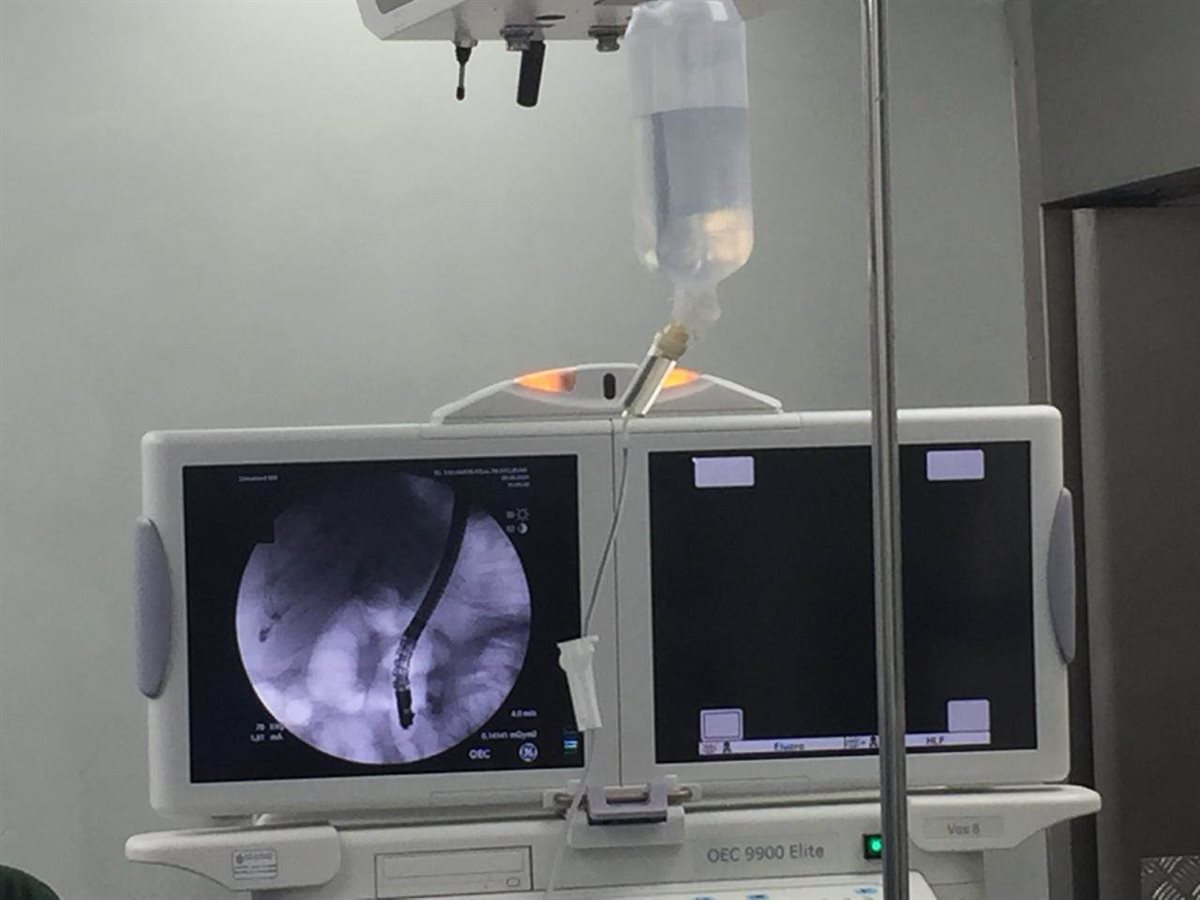

بينما أجرى العملية الثانية الدكتور أحمد مدكور أستاذ الجهاز الهضمي والمناظير بجامعة حلوان، حيث تم استخراج الحصوات من القنوات المرارية مع توسيع القنوات المرارية بواسطة منظار الجهاز الهضمي العلوي لمريضة تبلغ من العمر (86عام)، وذلك تمهيدًا لإجراء عملية استئصال المرارة لها بواسطة المنظار الجراحي أيضًا، وهي تحت الملاحظة الآن بالمستشفى.